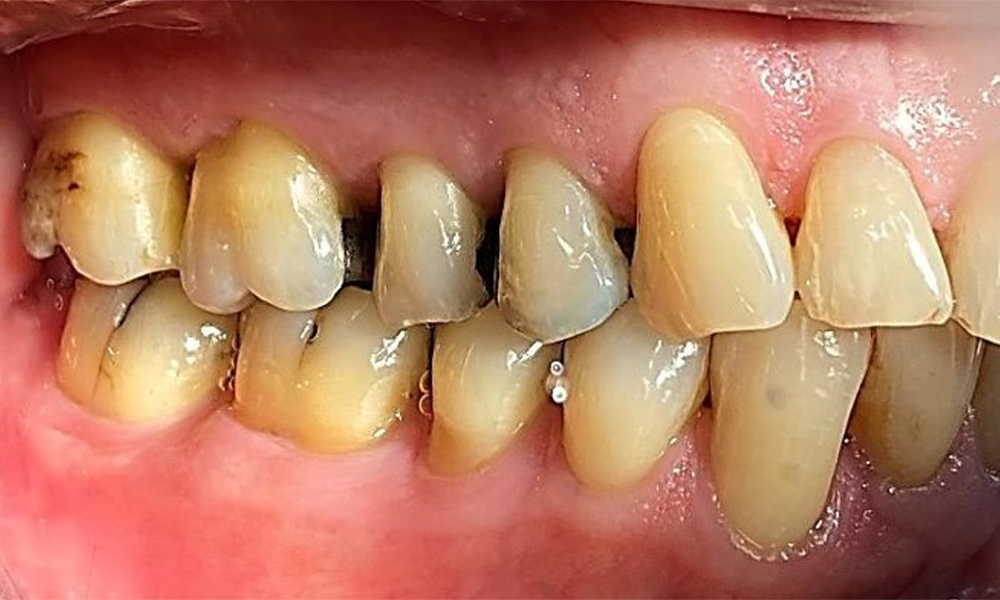

Der Patient hat ein vollbezahntes Gebiss mit 28 Zähnen, an welchen sich im Molaren- und Prämolarenbereich Amalgamfüllungen und Compositefüllungen befinden. An Zahn 14 zeigt sich ein sichtbarer klinischer Randspalt. Zahn 27 hat ein suffizientes Goldinlay. Zudem zeigen sich generalisierte Attritionen und Abrasionen. (Abb. 2, Abb. 3, Abb. 4, Abb. 5, Abb. 6)

Der Patient hat eine Parodontitis Stadium II, Grad B (5). Die klinischen Sondierungstiefen liegen mit 1-3mm im physiologischen Bereich. Lokalisierte Sondierungstiefen finden sich an 17 und 27 jeweils mesiopalatinal mit 5mm. Es liegen generalisierte Rezessionen von 1-3mm vor mit partiellem Verlust der Interdentalpapillen (Abb. 2, Abb. 3, Abb. 4)